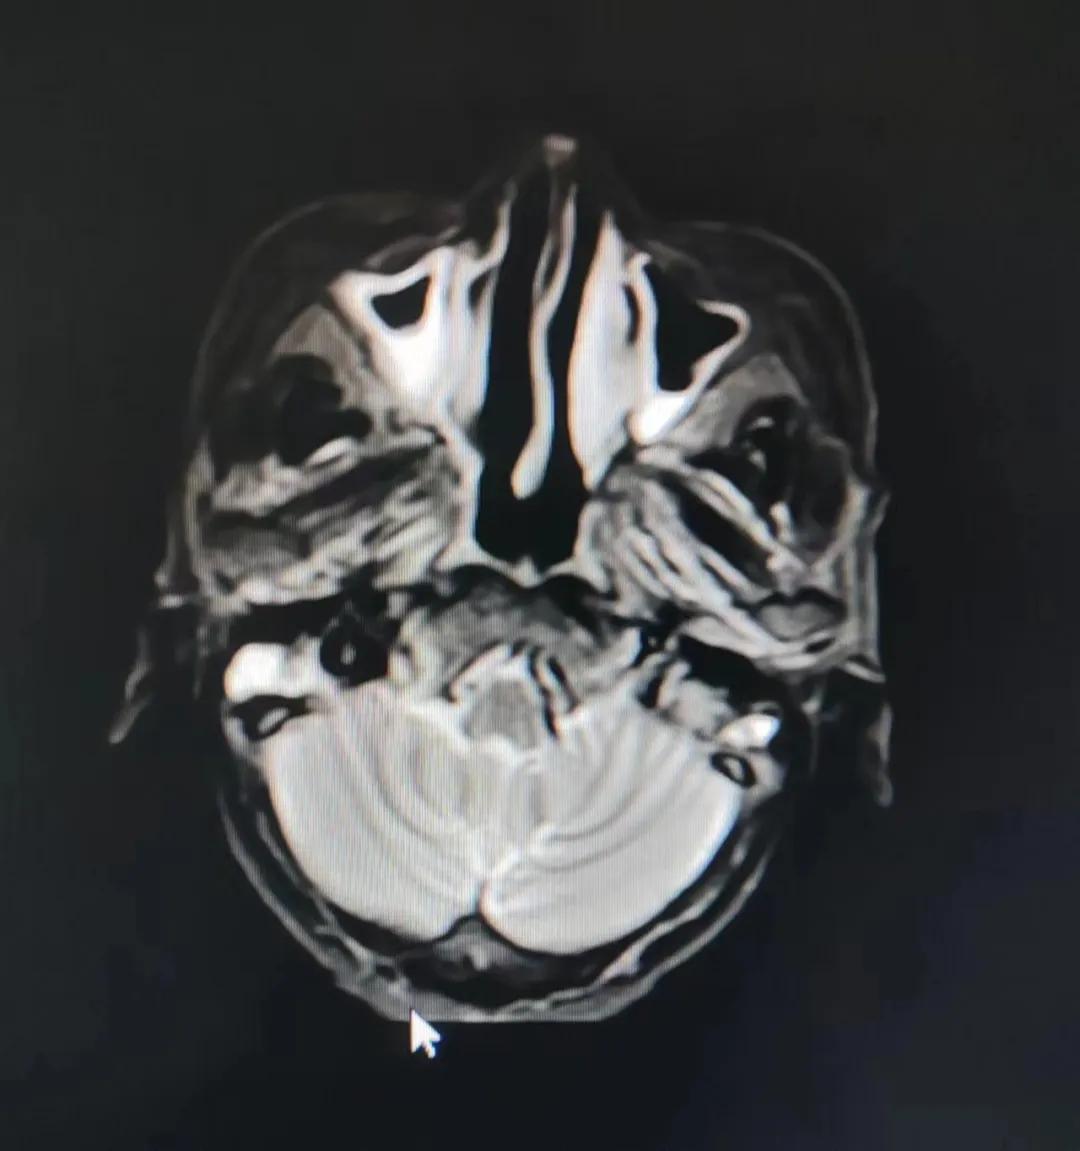

治療前

老人因鼻部腫物堵塞鼻腔并且侵犯鼻咽導(dǎo)致鼻塞、疼痛、吞咽困難,身心都備受煎熬,趙亮主任在詢問其病史期間幾度落淚。趙亮主任向患者及家屬解釋說:“現(xiàn)代放療比過去的傳統(tǒng)放療設(shè)備先進(jìn),技術(shù)不斷提升,能對腫瘤區(qū)域的照射劑量進(jìn)行優(yōu)化,做到準(zhǔn)確定位、精準(zhǔn)照射,同時,最大限度地降低正常組織的受量,對全身情況影響很小。”

考慮到患者年齡較大、體質(zhì)差,手術(shù)難度大,且常規(guī)的放射治療難以保護(hù)患者晶體造成患者雙眼視力損傷,放療團(tuán)隊(duì)以最快的速度制定了精準(zhǔn)放射治療方案并開始為其實(shí)施治療。僅僅數(shù)日后,老人腫塊出血即得到控制,腫塊明顯縮小,放療20次后腫塊迅速縮??!